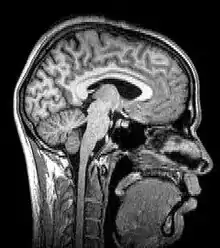

Although MRI (magnetic resonance imaging), optical coherence tomography and ultrasound are transmission methods, they typically do not require movement of the transmitter to acquire data from different directions. In MRI, both projections and higher spatial harmonics are sampled by applying spatially-varying magnetic fields; no moving parts are necessary to generate an image. On the other hand, since ultrasound and optical coherence tomography uses time-of-flight to spatially encode the received signal, it is not strictly a tomographic method and does not require multiple image acquisitions.

Magnetic resonance imaging or nuclear magnetic resonance tomography Nuclear magnetic moment MRI or MRT